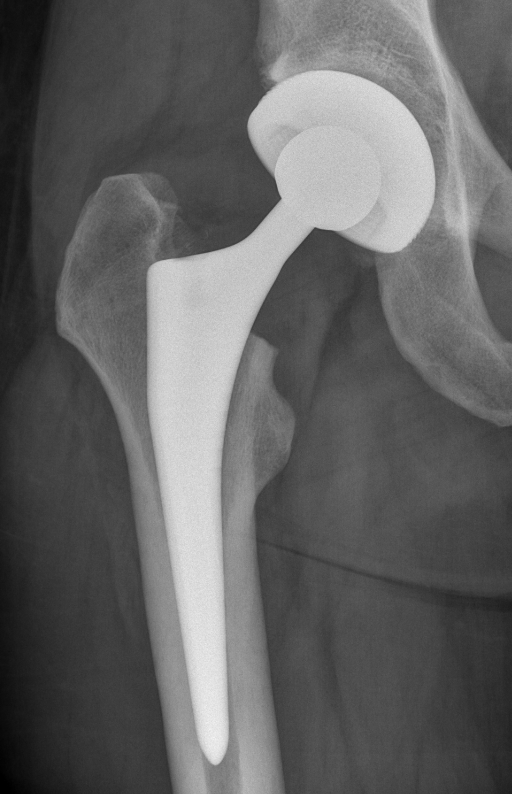

Für die Ursachenfindung bei schmerzhafter Hüftprothese ist eine detaillierte Patientenbefragung (Anamnese) wichtig. Wichtig ist zu erfahren, seit wann die Beschwerden genau bestehen und ob es einen Auslöser dafür gab. Neben der Lokalisation der Schmerzen ist es ebenfalls wichtig zu wissen, wann der Schmerz genau auftritt (immer, nur bei Belastungen, nur bei gewissen Bewegungen). Informationen zu Nebenerkrankungen, durchgemachten Infektionen oder erfolgten Zahnbehandlungen sind ebenfalls notwendig. Nach der Patientenbefragung findet eine Inspektion und detaillierte klinische Untersuchung statt. Dabei werden die möglichen Ursachen weiter eingegrenzt. Zusätzlich wird ein konventionelles Röntgenbild der Hüfte aufgenommen. Anhand diesem kann in gewissem Masse bereits die Prothesenlage und eine allfällige Lockerung beurteilt werden.

Im Vergleich zum Vorbild (links) zeigt sich im konventionellen Röntgenbild (rechts) ein Lockerungssaum (aus Bindegewebe) um den Prothesenschaft.

Bilder: Universitätsklinik Balgrist